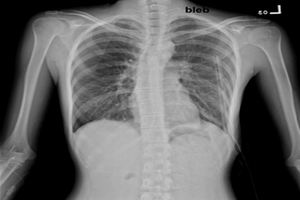

X線檢查:氣胸的典型X線為肺向肺門萎陷呈圓球形陰影,氣體常聚集於胸腔外側或肺尖部,此部透亮度增加,無肺紋。氣胸延及肺下部時肋膈角顯示銳利。少量氣胸時積氣多局限於肺尖,易被鎖骨影遮掩。此時,深呼氣相的X線徵象有助於診斷。部分自發性氣胸患者由於胸膜粘連分隔而呈現為“局限性氣胸”,積氣影可能被肺或縱隔遮掩,需轉動體位透視檢查方能發現。

1.X線檢查是診斷氣胸最可靠的方法,可顯示肺萎縮程度、有無胸膜粘連、縱隔移位及胸腔積液等。氣胸側透明度增強,無肺紋理,肺萎縮於肺門部,和氣胸效界處有清楚的細條狀肺邊緣,縱隔可向健側移位,尤其是張力性氣胸更顯著;少量氣胸則占據肺尖部位,使肺尖組織壓向肺門;如有液氣胸則見液平面。

診斷1.自發性氣胸加重期繼發於COPD的閉合性氣胸,有時甚至是開放性氣胸常被誤認為COPD加重期。氣胸患者氣促突出,並多為突然發生或進行性加重,而咳嗽、咳痰則相應較輕;COPD加重期常以氣候變化為誘因,以上感為先導,突出表現為咳嗽、咳痰加重、膿痰。積氣征是局限或單側的,兩側不對稱,而肺過度充氣征多是瀰漫的、雙側的;新出現的氣管移位更是氣胸有力佐證。X線檢查及必要時的人工氣胸機診斷性穿刺並測壓更可幫助確診。

2.肺大皰少量或局限性氣胸有時需與肺大皰相鑑別。肺大皰發生髮展非常緩慢,臨床表現一般比較穩定;X線胸片上透亮度增加的區域內仍可見細小條紋影,複習比較往昔胸片病灶變化不大;診斷性穿刺排氣後大皰影大小不變而有別於氣胸。